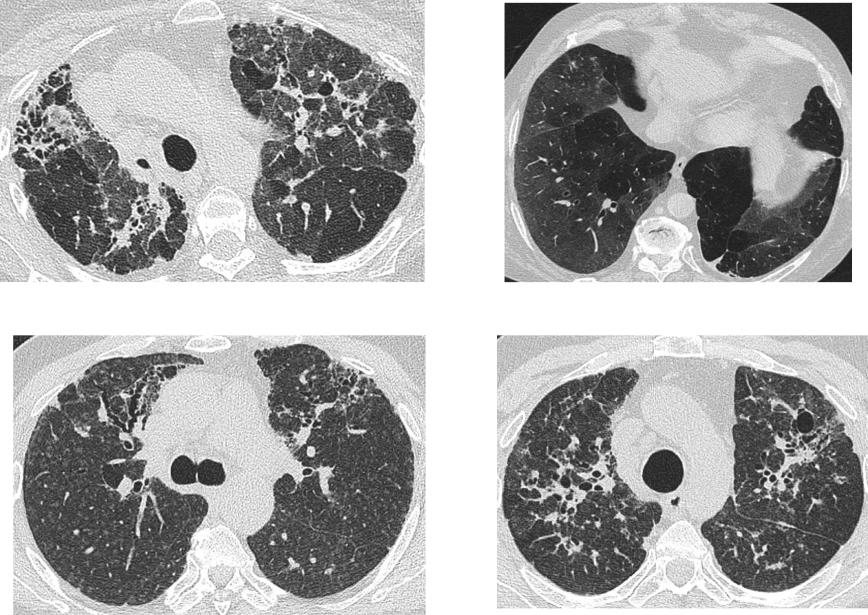

КТ-паттерн, неопределенный для ОИП

Распределение

Вариабельное или диффузное

КТ признаки

наличие фиброза с некоторыми чертами, характерными для паттерна «не-ОИП»

КТ-паттерн более характерный для диагноза «не-ИЛФ»

Фиброз с преобладанием в верхних

Любое из следующих:

и средних отделах

Преобладающая консолидация

Перибронховаскулярное

Протяженные поля чистого матового

предоминирование с сохранением

стекла (без обострения)

субплевральных отделов

Выраженное мозаичное уплотнение с

четкими признаками лобулярных

воздушных ловушек во время выдоха

Диффузные узелки или кисты

Lynch D et al. Lancet Respir Med 2017; http://dx.doi.org/10.1016/S2213-2600(17)30433-2

Мозаичное уплотнение

Профузные изменения по типу ‘чистого’

матового стекла

Узелки

Бронхоцентричность